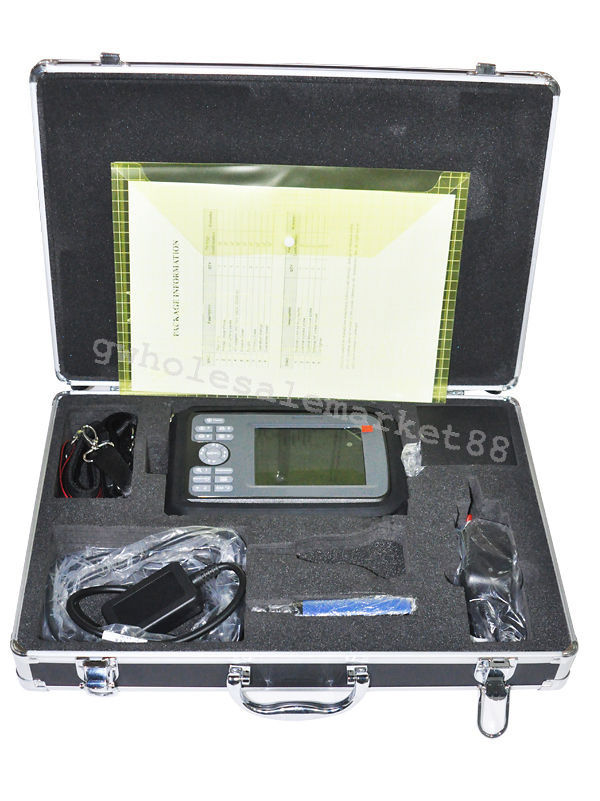

Condition: New: A brand-new, unused, unopened, undamaged item in its original packaging (where packaging is applicable). Packaging should be the same as what is found in a retail store, unless the item is handmade or was packaged by the manufacturer in non-retail packaging, such as an unprinted box or plastic bag. See the seller's listing for full details. See all condition definitions- opens in a new window or tab ... Read moreabout the condition

One of the standout features of this laptop ultrasound scanner is its portability. Weighing less than conventional ultrasound machines, it allows healthcare professionals to bring it right to the patient’s side. Plus, the user-friendly interface simplifies the operation, making it suitable for medical staff of all experience levels. Also, the compact size ensures that it fits easily into tighter spaces, such as small clinics or in-home care environments.